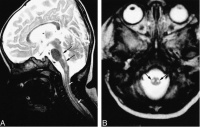

患者,女,35岁,湖南衡阳市郊农民。因行走无力,视物模糊5天,加重伴

言语不清,嗜睡2天,于2005年11月24日急诊入院。2005年11月20日上午,患者在广州某镇探亲时家务劳动后,上楼时出现行走无力,下午自觉视物模糊,不伴发热、恶寒、头痛、头晕、咳嗽、咽痛、恶心、呕吐等症状。11月21日上午患者步行到广州市某镇医院按“上呼吸道感染”治疗无效。11月22日下午患者出现行走无力加重,需人搀扶,并出现言语欠清晰、精神差,被家人于当晚送回湖南当地县人民医院诊治。查体:嗜睡,反应迟钝,言语欠清晰,口角向左歪,伸舌右偏,右上下肢肌力IV级,左上下肢肌力正常,病理反射(—)。头颅CT平扫未见异常。按“脑梗塞”治疗病情无好转,故于11月24日下午转至我院神经内科重症监护病房按重症脑梗塞诊治。入院时查体:T36.7℃P86次/分R20次/分BP105/71mmHg嗜睡,言语欠清晰,右眼睑稍下垂,右眼内收及左眼外展受限,右侧鼻唇沟稍变浅,伸舌右偏,双侧咽反射减弱,心、肺、腹均未见异常,左上、下肢肌力IV级加,右上、下肢肌力III级加,四肢肌张力稍低,腱反射减退,指鼻及轮替试验及感觉功能检查无法配合。颈软,克、布氏征(—),右巴氏征(+),左巴氏征(—)。实验室检查:血常规:WBC总数:10.4×109/L,分类正常;电解质、肝、肾功能血脂血糖血气分析均正常。11月25日上午患者出现昏睡,完全性失语,四肢肌力明显减退,右上肢肌力0级,左上、下肢及右下肢肌力均II级。查头颅MRI示:中脑与桥脑交界处见片状稍长T1稍长T2信号,边界欠清晰,中脑导水管及第四脑室未见明显受压;头颅MRI增强:脑干异常信号,未见明显强化,考虑脑干梗塞。11月26日患者陷入浅昏迷,腰穿查脑脊液压力95mmH2O,外观无色,清亮,潘氏实验(+),总蛋白定量0.58g/L,白细胞数76×106/L,单个核细胞90%,多个核细胞10%,葡萄糖2.59mmol/L,氯化物117mmol/L,故诊断为脑干脑炎,给予地塞米松10mg静滴,每日一次,同时予抗病毒,抗感染等治疗,12月2日患者意识转清醒,但言语模糊不清,右上肢肌力II级,右下肢肌力0级,左上下肢肌力II-III级。14天后停地塞米松改为口服强的松30mg/天,逐渐减量,患者入院第20天因经济困难出院,出院时查体:右眼内收及左眼外展受限,伸舌稍右偏,双上肢肌力III-IV,双下肢肌

讨论:脑干脑炎临床表现多种多样,但缺乏典型的症状和体征,容易误诊。本病例患者以突发肢体瘫痪起病,发病前无感染史及病程中无发热史,头颅CT平扫未见异常,头颅

MRI增强:脑干异常信号,未见明显强化,考虑脑干梗塞。故临床误诊为重症脑梗塞。误诊原因可能为:(1)近年来青壮年脑梗塞发病率增高;(2)临床医生对突发肢体瘫痪和意识障碍患者,过分依赖头颅CT和MRI等影像学诊断结果;(2)发病前无感染史及发病前后病程中无发热史导致忽视了炎性疾病的可能。文献报道脑干脑炎的发病特点为:1.任何年龄都可发病,以青壮年居多。2.大多患者发病前1—4周有上呼吸道感染或其他病毒感染史。3.起病急骤,往往早期出现精神症状和意识障碍,通常在较短时间内出现双侧脑神经麻痹,伴有一侧或双侧的肢体运动障碍感觉障碍,但长束征少见,症状和体征较弥散很少局限于某一部位,4.脑脊液基本正常,蛋白轻度增高,细胞以淋巴细胞和单核细胞为主。5.病程常有自限性,经7—8周治疗后大部分好转或痊愈。6.激素早期治疗有效,预后好。7.头颅CT和MRI的异常率低。本例开始按脑梗塞治疗效果不佳,发现脑脊液异常后,按脑干脑炎以地塞米松等治疗,患者完全康复。我们推测该病发病机制可能是病毒的直接侵润损伤或病毒感染后的免疫损伤。MasaakiOdaka等研究认为许多Bickerstaff脑干脑炎患者都合并有Guillain-Barre综合征轴突改变,暗示这两种病是相近的,二者属于同一疾病谱。